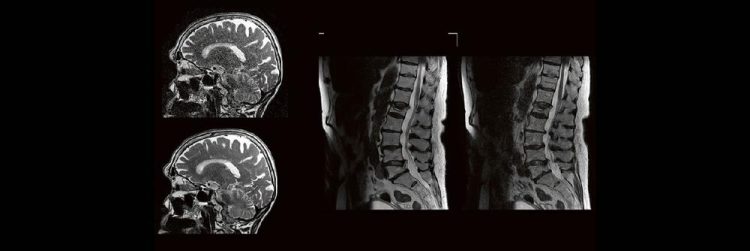

Blickdiagnosen im MRT für MTR (Webinar | Online)

Dorina Petersen In der täglichen Routine hat man wenig Zeit, sich lange mit den Bildern zu beschäftigen, die man anfertigt. Dennoch soll man auf bestimmte Erkrankungen richtig reagieren und die Protokolle anpassen. MTR´s sind keine Ärzte, dennoch gibt es ein Krankheiten, die eindeutige Bildmerkmale zeigen. In diesem Webinar werden eine Reihe solche Erkrankungen gezeigt. Woran…Continue reading Blickdiagnosen im MRT für MTR (Webinar | Online)

DEEP-Learning-Rekonstruktion in der Neuroradiologie (Webinar | Online)

Professor Dr. med. Marc Brockmann WEITERENTWICKLUNGEN VON KOPF BIS FUSS BEIM VC Oberstarzt Dr. med. Stephan Waldeck DEEP-LEARNING-REKONSTRUKTION IN DER NEURORADIOLOGIE Die CT ist ein essentielles Routine-Verfahren in der Neuroradiologie. Bei steigender Bildqualität konnte die Röntgendosis mit neuen Technologien in der letzten Dekade deutlich gesenkt werden, was für die zielgerichtete und möglichst schonende Behandlung von…Continue reading DEEP-Learning-Rekonstruktion in der Neuroradiologie (Webinar | Online)